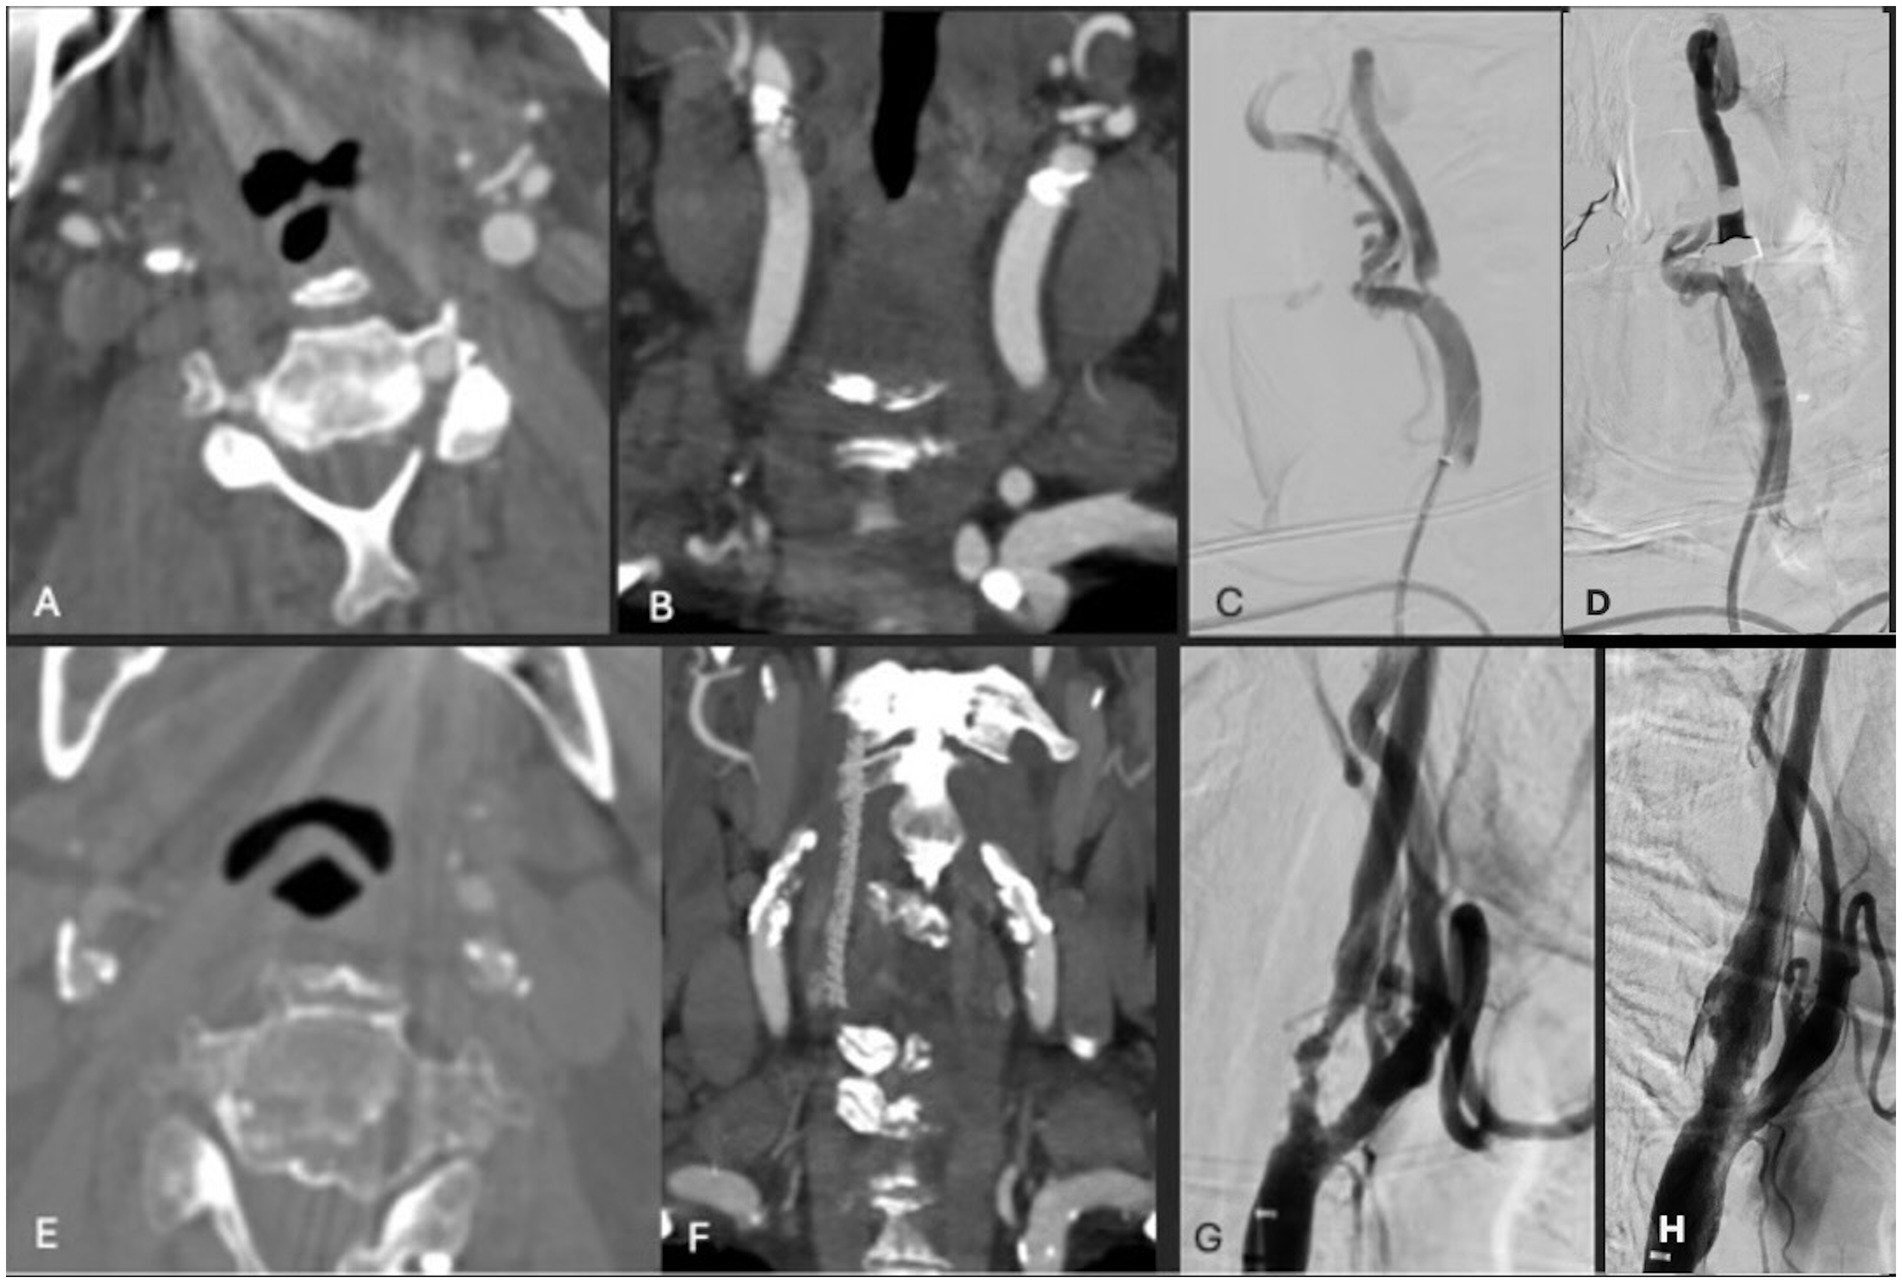

Figure 1. (A,B) Axial and coronal CTA demonstrating right ICA circumferential calcified stenosis. Catheter angiography demonstrating (C) severe R ICA stenosis with (D) significant improvement in caliber and flow within right ICA following lithotripsy, stent and angioplasty. (E,F) Axial and coronal CTA demonstrating right ICA circumferential calcified stenosis. Catheter angiography demonstrating (G) severe R ICA stenosis with (H) significant improvement in caliber and flow within right ICA following lithotripsy, stent and angioplasty.

A patient in their 80s presented with left homonymous hemianopia and dizziness (Table 1). CTA revealed greater than 80% stenosis of the right ICA. Associated right hemispheric watershed punctate infarcts were noted on diffusion-weighted MRI. The level of the carotid bifurcation with severely calcified stenosis was located high in the neck and deemed surgically accessible; therefore, CAS with concomitant IVL was recommended over CEA. One episode of sonic pulses was released over 1 min, with approximately one sonic pulse cycle per second (Figure 1). The patient was neurologically intact following the procedure. Post-angiogram ultrasound showed a peak systolic velocity (PSV) of 106 cm/s in the ICA/stent with no significant stenosis visualized within the stent. The PSV ICA/CCA ratio was 1.7 with a normal vertebral artery waveform. Following the stenting procedure, the patient experienced transient hypotension followed by left-sided drift. MRI was completed at that time, showing small foci of acute infarctions in the right frontal lobe and right corona radiata. It was found that the P2Y12 reactive unit assay suggested they were non-responders, and therefore, clopidogrel was stopped and ticagrelor was initiated. The patient was discharged to inpatient rehabilitation after an 8-day hospital stay. At the 3-week follow-up, they had no visual deficit, and the left-sided weakness had resolved. The patient was then transferred to an outside hospital for further care.

A patient in their 70s presented with a transient ischemic attack (TIA) that manifested as a right eye vision disturbance. CTA revealed 90% occluded right ICA. MRI was obtained and showed no acute infarct. Given the patient’s concurrent advanced heart failure, history of coronary artery bypass graft, and cervical laminectomy and instrumented fusion, they were deemed unfit for general anesthesia and carotid endarterectomy. IVL with stenting was performed with 2 episodes of pulses (Figure 1). Post-angiogram ultrasound showed a PSV of 102 cm/s in the right ICA with a PSV ratio of 1 in the ICA/CCA. There were no post-procedural complications, and the patient was discharged in stable condition 1 day following the procedure. At the 3-week follow-up, the patient was clinically stable with no observed or reported neurological deficits, aside from a baseline mild facial droop. However, the patient unfortunately died 7 months following the procedure secondary to an acute exacerbation of chronic heart failure.